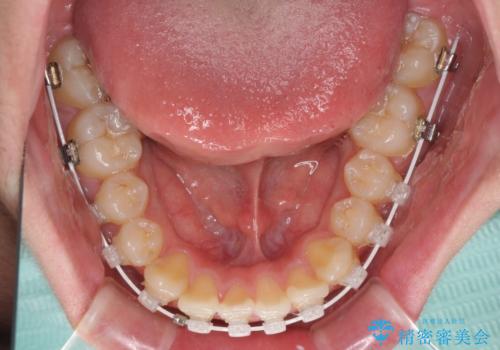

- 矯正装置

- 審美装置

- 上下前歯のデコボコを改善したいとのことで来院された患者様です。

自己管理を減らしたいとのことで、ワイヤー装置による矯正治療を行うこととしました。

中学生と言うこともあり、1年強の短期間で終了しました。

歯磨きがしっかりとできないと虫歯になるリスクがありましたが、治療期間中は清潔な状態を保っていただけました。